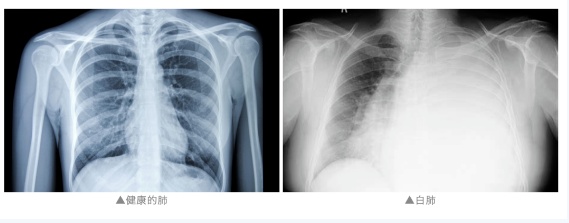

“两个肺都是白的,发现的时候是甲流,而且是混合感染。”江都人民医院重症医学科主任陈齐红介绍,陈女士患有糖尿病多年,免疫力偏低,得了流感后硬扛,大大增加了肺部的感染风险,最终导致“白肺”。

通常来说,“白肺”指急性呼吸窘迫综合征,主要发生在重症感染时,是肺组织炎症渗出等病变导致的一种影像学表现,“白肺”患者常常病情较为严重,预后较差。